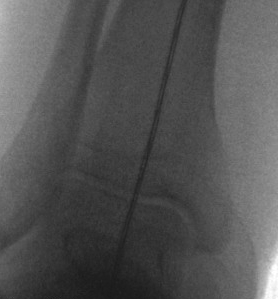

C. Intra-operative check

Use diathermy lead / drop rod

- center femoral head to center on talus

- ensure passes over lateral tibial spine / Fujisawa point